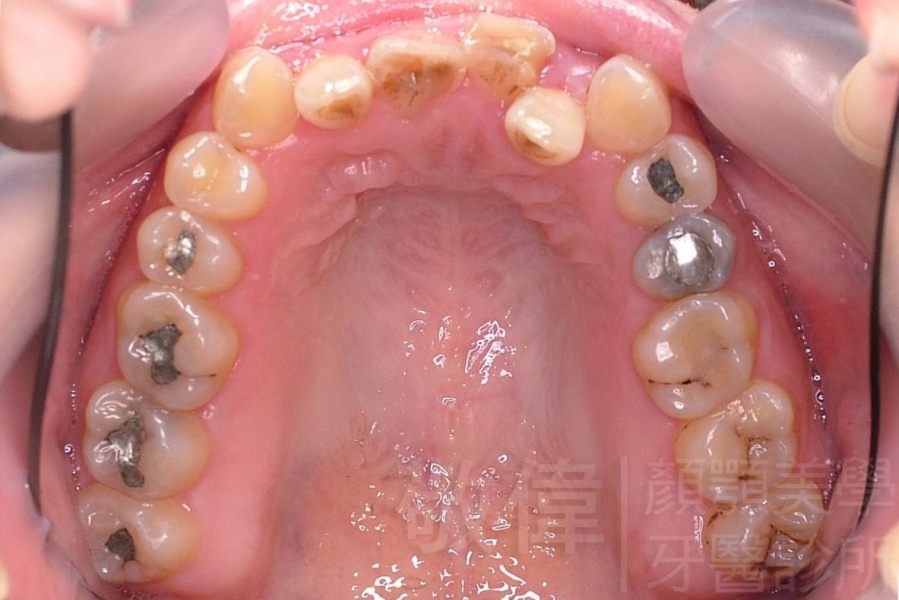

齒顏矯正/戽斗、亂牙、爛牙,變身 免植牙的健牙美女

變臉矯正,原來戽斗妹跟大歪臉變成自信正妹

經由本院3D數影X光影像儀分析、與3D齒顎顏矯正技術,再配合口腔顎面正顎專科醫師施以正顎手術治療,雙方共同合作,使患者臉部外觀有很好的改善,大歪變小歪,產生了天南地北的大改變,她的人生也整個變得不一樣。